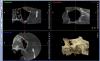

Andex Опубликовано 29 июля, 2013 Автор Поделиться Опубликовано 29 июля, 2013 Сегодня пациентка принесла 3д снимки. Артефакт видимо не сообщается с пазухой Высота кости до дна пазухи 2 мм Коллеги, надеюсь на ваши советы, учитывая что это будет первый синус вопросы отстаются теже из первого сообщения : 1) что за артефакт в пазухе? и если это неизвестно что(жалоб никогда на него не было), то не помешает ли он проведению субантральной аугментации?2) после препарирования окна, когда нужно отславиать мембрану Шнайдера - мне надо под нее класть резорбируемую мембрану,а уже только под нее графт(чтобы она как бы укрыла графт сверху?) или это некопентентный вопрос?3) как в данном случае быть,если при отслаивании порвется мембрана шнайдера(а я думаю при первом моем разе я ее не смогу аккуратно отодвинуть), какую тогда технику применить?-имею ввиду как в таком случае класть графт(и надо ли его укрывать мембраной,подкладывая ее под порванную шнайдеровоскую?)4) что проще и безопастнее(и процент удачи выше) - одновременно поставить импланты в позиции 25 и 26(или 25 и26), хватит ли 3 мм для их первичной стабилизации? или это очень трудно и для первого раза сделать только один синус без имплантации? 5) Может быть для первого раза выбрать какой нибудь более подходящий случай и не задавать "простых" вопросов?Заранее благодарен откликнувшимся! Ссылка на комментарий

АнтонТЛТ Опубликовано 29 июля, 2013 Поделиться Опубликовано 29 июля, 2013 (изменено) 1. Что за артефакт, можно только гадать. Мне кажется он сообщается с пазухой. Достал бы со стороны нёба после откидывания лоскута.2.,3. Если порвете кладите мембрану, под нее графт. Если не порвете, не кладите. Начинайте отслойку дистально, потом низ, потом медиально, потом переходите на внутреннюю стенку пазухи. Графт. На окно мембрану.4. Без имплантатов. Изменено 29 июля, 2013 пользователем АнтонТЛТ 3 Ссылка на комментарий

Andex Опубликовано 21 августа, 2013 Автор Поделиться Опубликовано 21 августа, 2013 Всем добрый вечер. Вдохновленный кейсами уважаемых докторов с форума, сделал свой первый открытый синус. Фото до и после. Ниже опишу последовательность действий, чтобы можно было понять где допущены ошибки.Отслоился - перед формированием окна решил собрать аутокость с передней стенки пазухи. Сначала шабером от HLW - не чего не собрал, затем скребок Hu-fridy - собрал нормально, но от излишнего усилия, провалился скребком через переднюю стенку прямо в пазуху - естественно перфо мембраны шнайдера. Затем окно с помощью набора SLA, под мембрану шнайдера положил special (osteobiol), под нее mp3 и смесь гранул Gen-oss с аутокостью. Хотя предварительно и сушил губкой - все же половину наверно вымыло обратно, окно закрыл evolution, ушился. Что вижу я - недоотслоился до медиальной стенки - соответсвенно там кости не будет наверное, как то умудрился скребком проколоть кортикалку пазухи...Хотел бы услышать критику по данному кейсу)Дальнейшие реккомендации - через 6 мес винты с повторным синусом? Болььше тренироваться на обучающих пациентах ? Ссылка на комментарий

Alexey Doc Опубликовано 21 августа, 2013 Поделиться Опубликовано 21 августа, 2013 Главное, начало положено хоть и не совсем удачное!Серьезных практических советов дать не могу потому что с пазухами пока общаюсь только по средством гайморотомий, а лифтинги делаю на яйцах и на животных. Судя по снимку графт распределен очень неравномерно, а медиально по моему вообще отсутсвует. Ссылка на комментарий